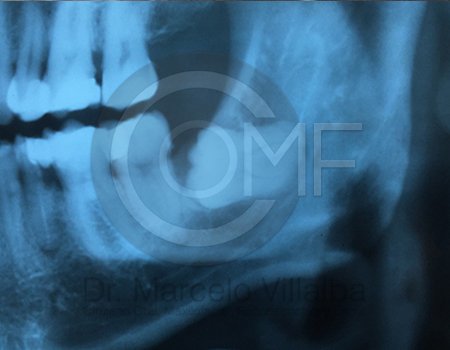

Antes de la extracción se realiza una valoración clínica y estudios de imagen, como radiografías panorámicas o tomografías, para conocer la posición del tercer molar, su relación con los nervios y planificar un procedimiento seguro y adecuado para cada paciente.

No es recomendable. Antes de extraer terceros molares es necesario realizar una valoración clínica y estudios de imagen para conocer la posición del diente, su relación con los nervios y el tipo de procedimiento más seguro para cada paciente.